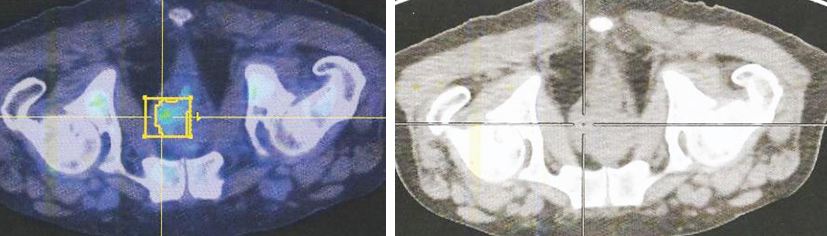

2. PET scan – 20 September 2022.

There is a FDG-avid lesion at the left prostate lobe measuring 1.8 x 2.2 cm.

There are multiple small lung nodules scattered in both lungs,

largest measuring up  to 0.8 x 0.7 cm at the right lung base.

There are multiple FDG-avid bone lesions along: bilateral humeri, bilateral scapulae, bilateral clavicles, manubrium-sternum, multiple bilateral ribs, along the spine, pelvic bones (bilateral ilium, pubic bones) and along bilateral femur.

Some of the bone metastases have extraosseous soft-tissue components, particularly at thoracic vertebrae (T7, T8 and T 11 vertebrae) and left ilium.

Impression:

1. Lesion at left prostate lobe likely corresponding to primary prostate carcinoma.

2. Multiple bilateral lung nodules – suspicious for lung metastases.

3. Multiple bone metastases.